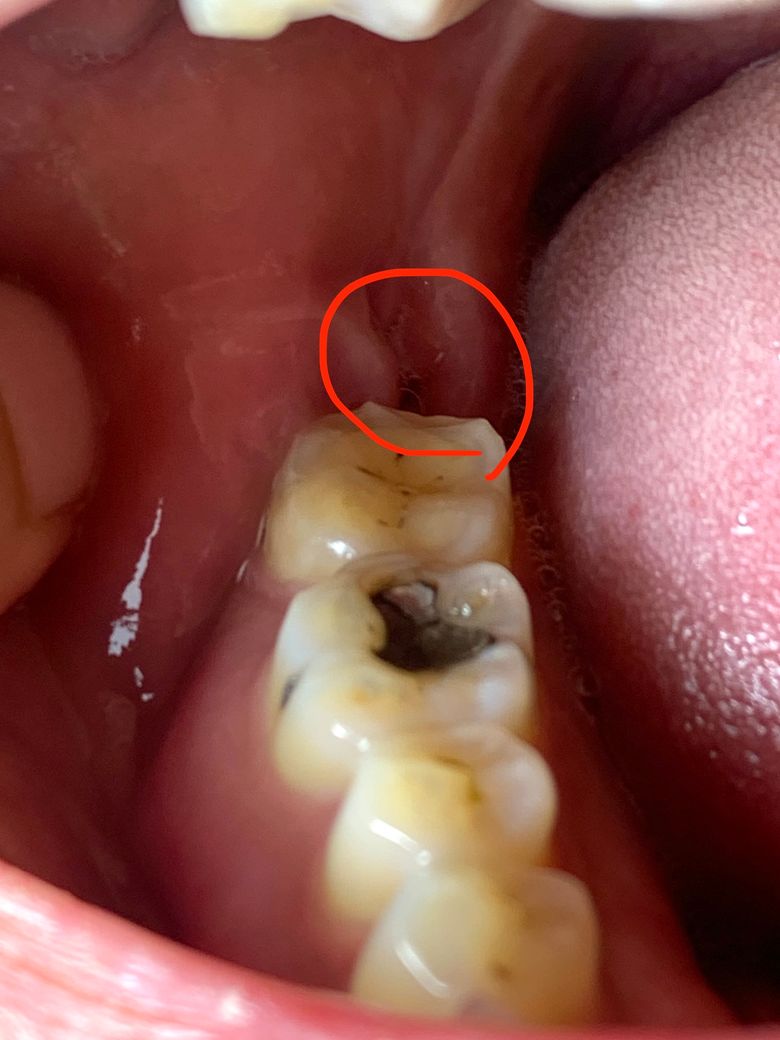

사랑니 발치 후 16일차인데 아직 통증이 있고 볼씹힘때문에 통증이 이어집니다 ㅠ 도와주세요

아래 오른쪽 사랑니 발치 16일차인데 극심하게 아픈건 사라졌는데, 여전히 아래 앞니가 시리고 오른쪽 볼이 씹힌건지 그 부분 잇몸이 땡땡하게 부어있어서 목이 살짝 아프고, 오른쪽 얼굴 피부가 예민하고, 오른쪽 머리에 약간 두통이 있는거 같아서 걱정되서 왔습니다 ㅠ 아직 사랑니 아래위로 약간 욱씬함이 있는거 같긴해요. 미국인데 드라이소켓 일주일 전에 판정받고 치료한 뒤, 조심하라는건 다 조심했거든요

한국에서 뽑고 2일뒤에 장거리 비행기 탔고, 초반에 약간 일정이 있어서 무리하긴 했어요 ㅠ 갑자기 뽑기 이틀전부터 엄청 사랑니가 아파서 뽑은 케이스긴 하거든요. 뽑을때도 뿌리가 깊고 뼈 끝이 뭉툭해서 1시간 정도 뽑았습니다 ㅠ 아래 사진 첨부합니다!